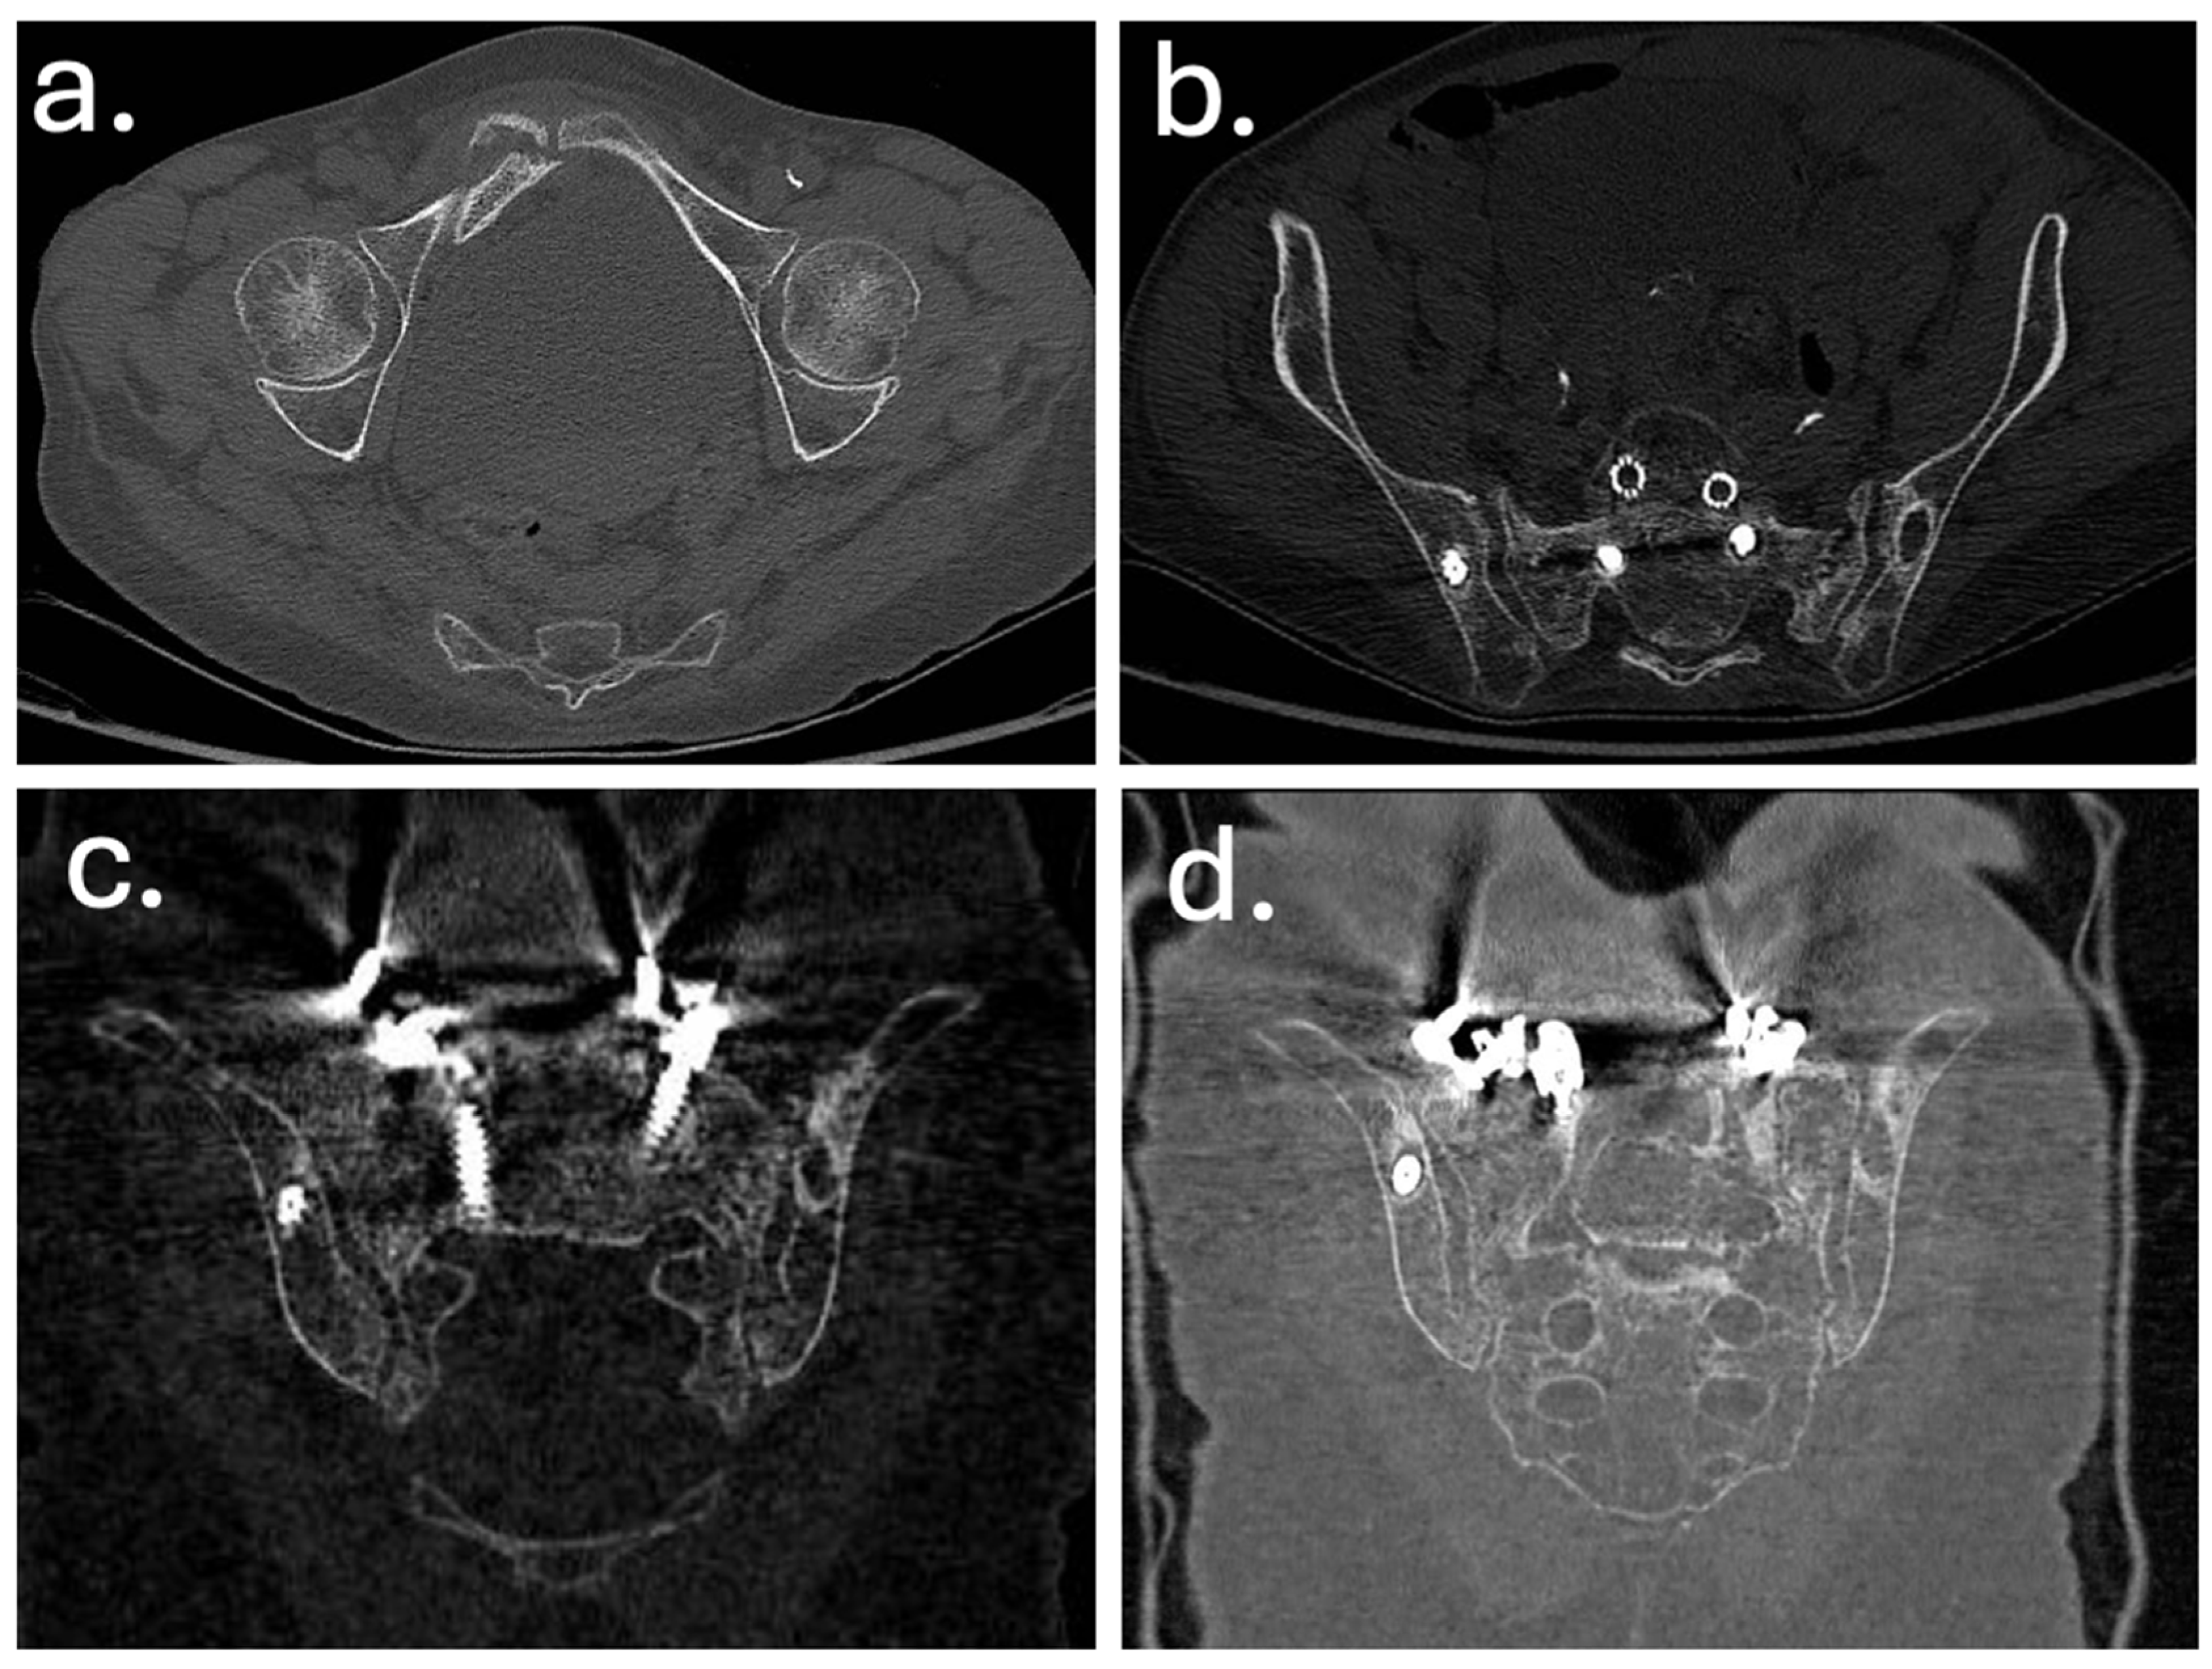

3. Case Report

| Year | Event |

|---|---|

| Dec 2010 | Posterior decompression and L5–S1 fusion |

| Apr 2012 | Posterior extension of fusion to L3 for junctional failure |

| Nov 2014 | Extreme lateral interbody fusion (XLIF) at L3–L4 and L4–L5 |

| Jun 2016 | Major revision from T7 to pelvis with bilateral iliac fixation |

| Aug 2016 | Postoperative infection (Acinetobacter baumannii XDR), multiple antibiotic courses |

| Dec 2019 | Removal of left iliac and T4–T5 screws, new fixation at T2–T3 with 4-rod construct |

| Jan 2020 | Rotational musculocutaneous flap for soft tissue coverage |

| Feb 2022 | Diagnosis of sacral insufficiency fracture (CT: left sacral ala right ilio-pubic branch fracture, with loosening of iliac screws) |

| Sep 2022 | Surgical debridement, rod shortening, V-Y fasciocutaneous flap |

| Mar 2025 | Removal of fractured proximal thoracic screws; cultures positive for Staphylococcus epidermidis and Ralstonia pickettii |

| May 2025 | Stable condition on suppressive antibiotics; no further revision indicated |